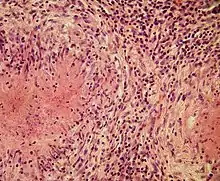

Fragment of the outer edge zone of tuberculosis epithelioid cell granuloma. In the lower part – a layer of epithelioid cells, in which Langhans giant cell begins to form, as a result of the fusion of epithelioid cells. In it, we can notice the division of the cell nucleus of epithelioid cells, from which smaller nucleus are formed. Single pycnotic and apoptotically altered macrophages are found among epithelioid cells. Above the zone of epithelioid cells is a layer of fibroblasts that form a kind of “capsule”. In the upper part – a layer of cells consisting of lymphocytes. The video shows the result of optical scanning (when using Phase-contrast microscopy) when changing the depth of field.

Epithelioid cells are an essential characteristic of epithelioid cell granulomas.[10] Epithelioid cell granuloma can be defined as specifically and structurally organized collection of epithelioid cells, macrophages, lymphocytes and dendritic cells. Foreign-body granulomas may be considered an organized collection of macrophages, including mere collections of giant cells surrounding inert substances like suture material – the so-called "non-immune granulomas." Granuloma formation is associated with pathogens that have learned to evade the host immune system by various means like resisting phagocytosis and killing within the macrophages. Indigestibility of matter by macrophages is a common feature of granulomatous inflammation.[4] Granulomas try to wall off these organisms and prevent their further growth and spread. Historically widespread and destructive diseases such as tuberculosis, leprosy and syphilis are granulomatous conditions. Granuloma formation is also the feature of many more contemporary conditions, like fungal infections, sarcoidosis and Crohn's disease.[4]